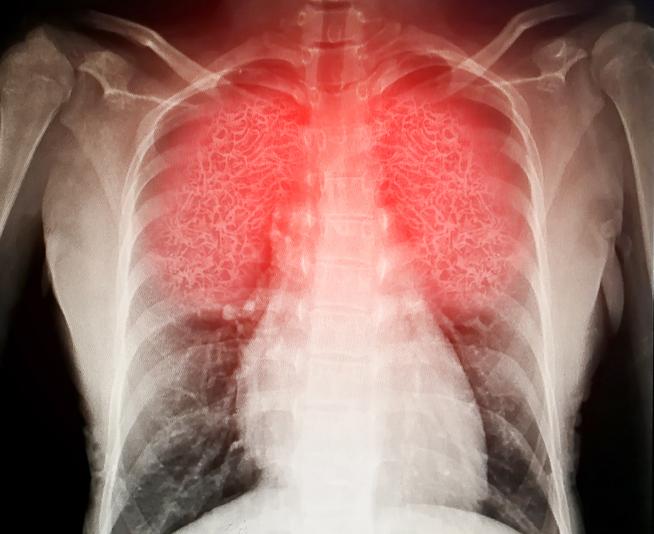

Es posible que se realice una radiografía de tórax para estar seguros del diagnóstico y ver la gravedad de la infección.